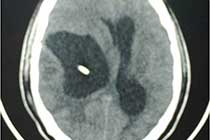

Brain Abscess Brain Abscess Post OP 2 Clinical Intra OP ,After Excising The Granuloma Intaop Scalp Abscess CT Scalp Abscess Cerebellar Abscess Post OP Clinical Cerebellar Abscess Brain TB Granuloma Post OP CT Scan Brain Infection Brain Abscess Preop MRI 2 Brain Abscess PRE OP Clinical 1 Brain Abscess PRE OP Brain Abscess Intraop 2 Brain Abscess Following Shunt Temporal Abscess T2W of TB Granuloma Scalp Abscess Preop CT Marking PRW OP MRI of TB Granuloma Post OP Clinical Photo Post OP Cerebellar Abscess Post OP Brain Abscess Intraop Specimen of Granuloma